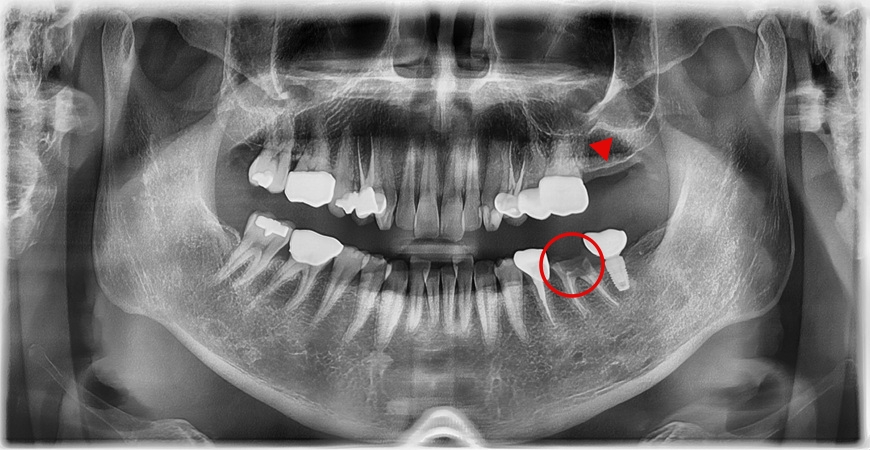

A male patient in his 40s visited our clinic stating that the gold crown on his lower left molar had come off. The crown fell out suddenly while he was eating, and at first glance, it might seem like a situation where one could think, “Isn’t it enough to just put the crown back on?” However, after carefully examining the condition of the remaining tooth following the loss of the gold crown, we found that the problem was deeper than expected.

Upon examination, the crown of the tooth was already severely decayed and had come out attached to the gold crown, leaving only the root inside the mouth, and inflammation was also observed internally.

If a certain amount of tooth structure remains above the gum line, it may sometimes be possible to save the tooth, but in cases like this, preserving the tooth is extremely difficult. Even if a crown were to be placed again, it would be unlikely to last long, and there would be a high possibility of recurring pain or reinfection. Therefore, we determined that the tooth was not restorable. After fully explaining the current condition and prognosis to the patient, we decided to proceed with extraction.

While planning the extraction, we also considered the timing of implant placement. Generally, implants are placed after waiting a certain period of time for the gums and bone to heal following extraction. However, in this patient’s case, the condition of the alveolar bone was good, and the inflammation was limited to a localized area, making immediate implant placement after extraction possible. Accordingly, we established a treatment plan to place the implant simultaneously with the extraction of the remaining root. At the same time, we also decided to place an implant in the second molar on the upper left side.